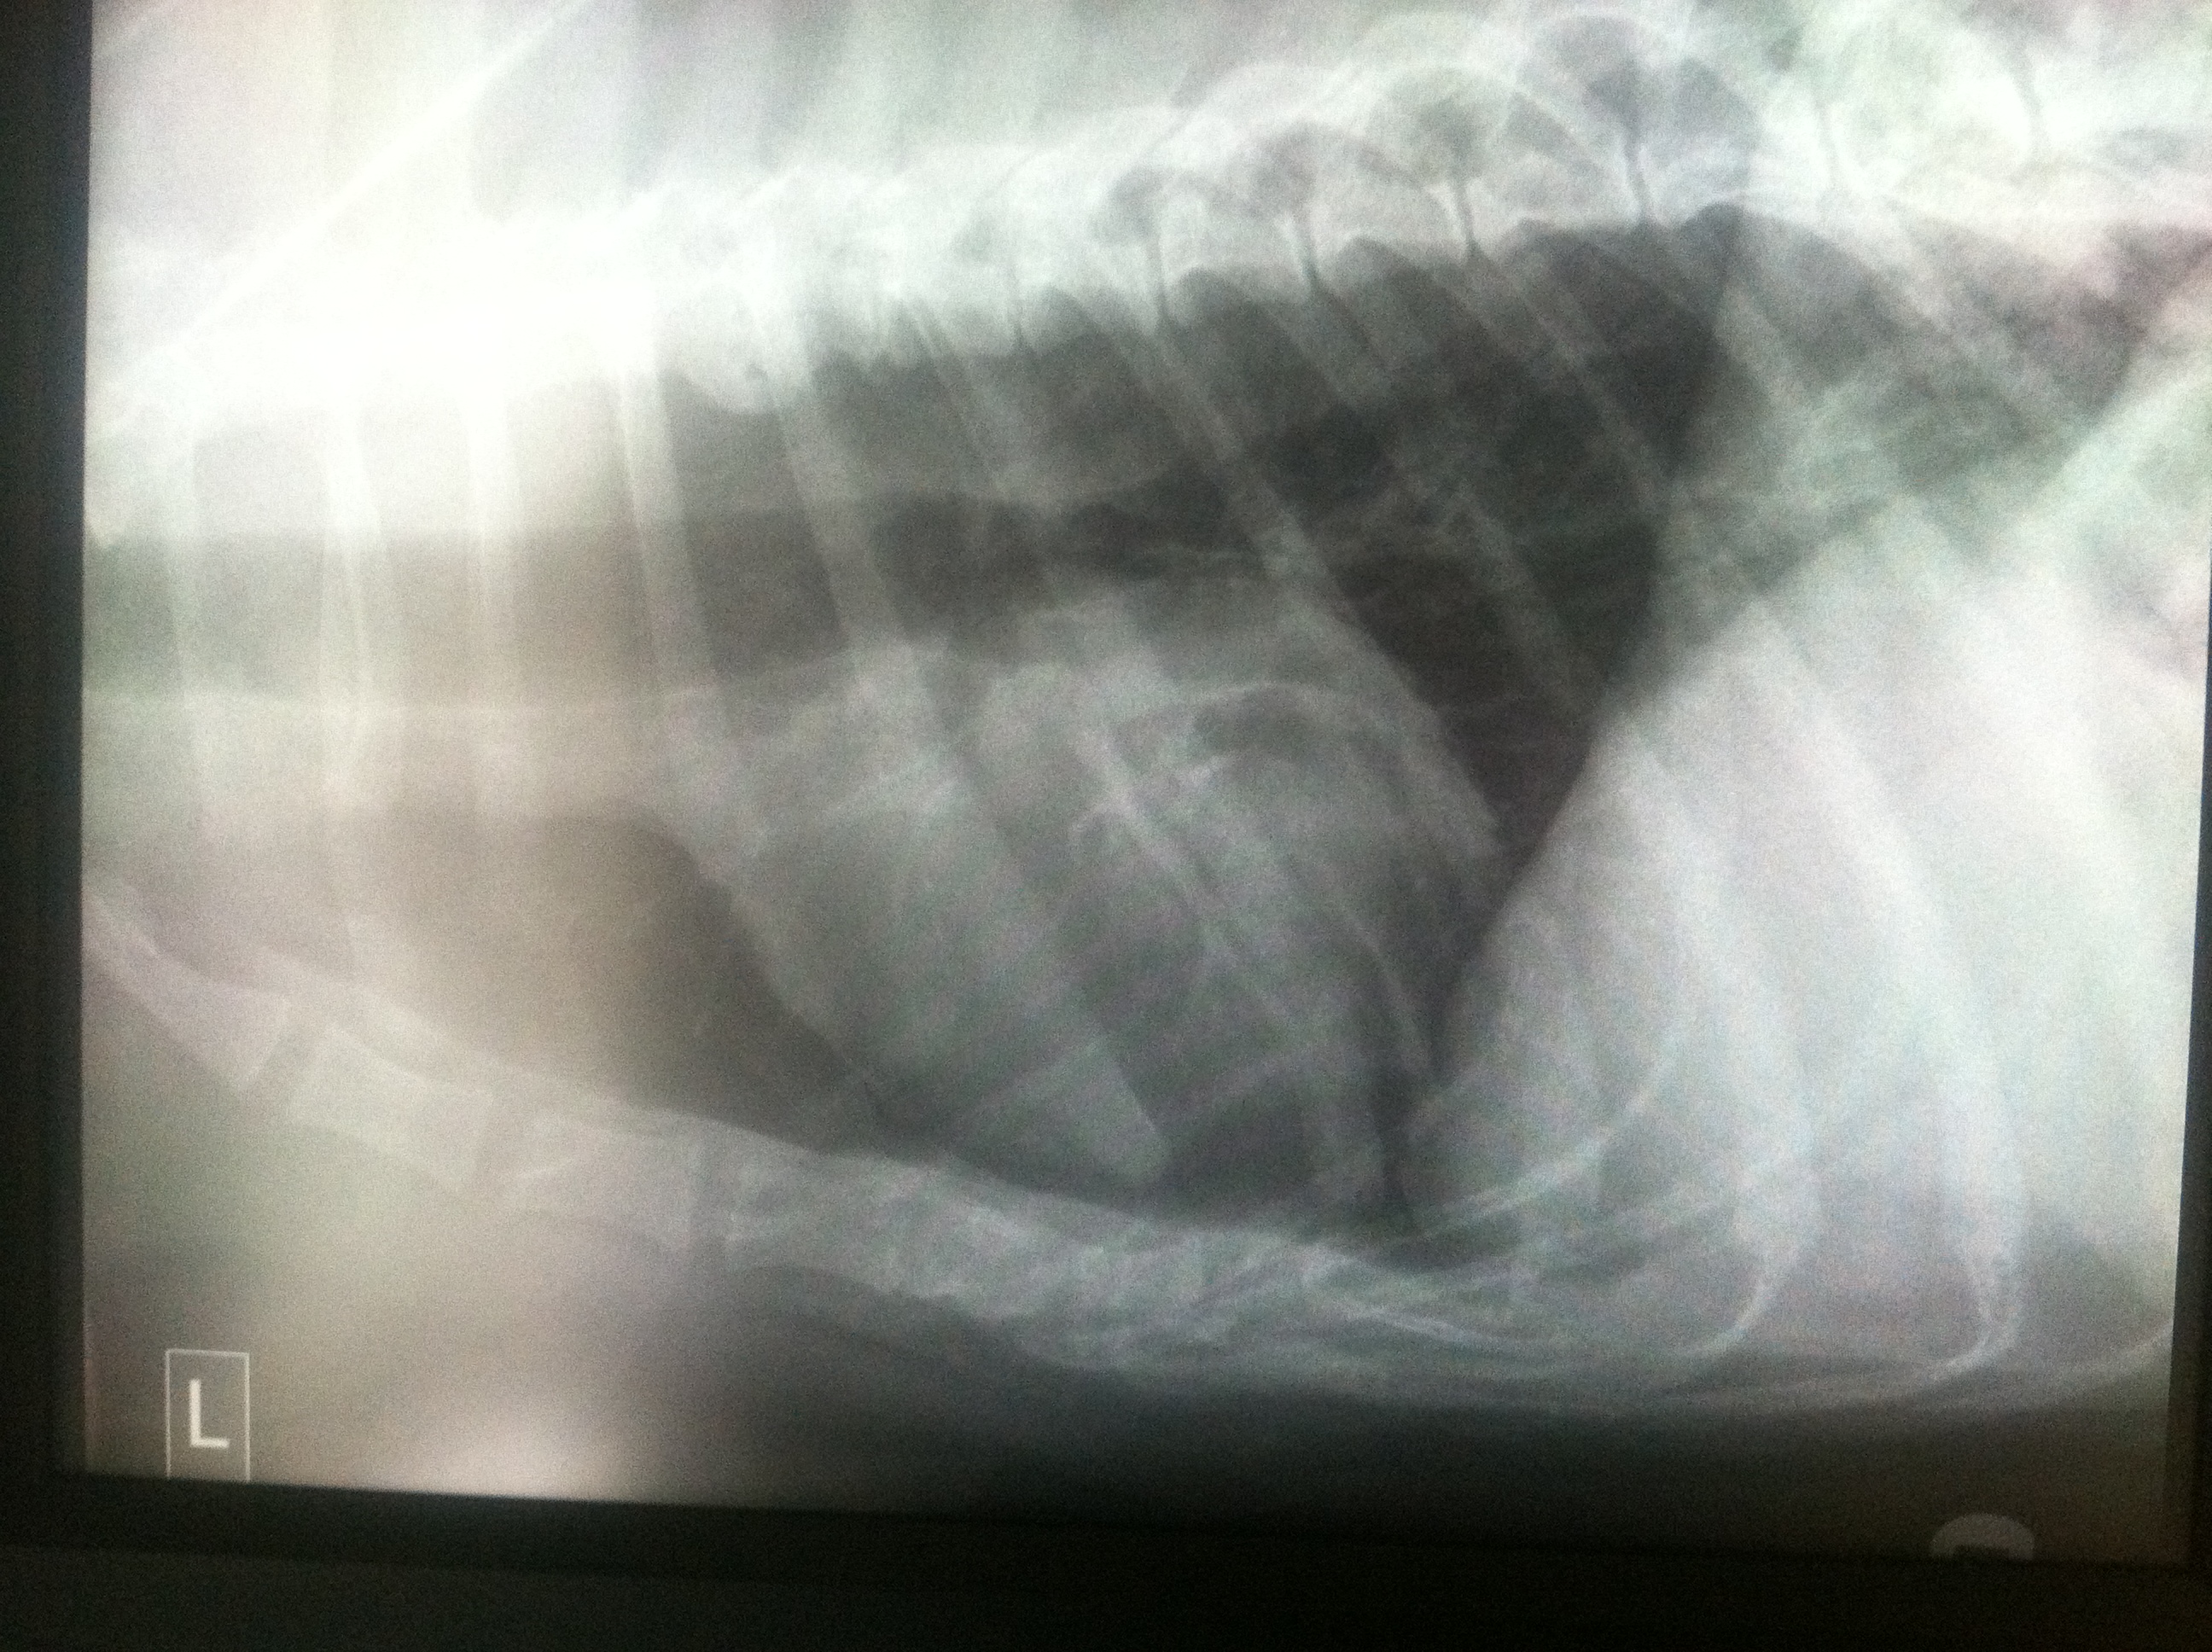

WEEK 2

I am not going to act like I know a lot about what these x-rays are showing because reading x-rays is not my forte, but I can tell you what was explained to me:

Pleural effusions appear on chest X-rays as white space at the base of the lung. Pleural effusion obscures the silhouette of the heart

It’s really hard to see Sherman’s lung in these small pictures but you can see the white space in the top two pictures and his heart has obvious loss of details compared to the 3rd x-ray.

Pnuemothorax means air in the chest cavity.

In the first 2 pictures there is mild pneumothorax in Sherman’s chest cavity.

Again, it’s hard to see in these pictures. Taking x-rays of the chest of a giant breed dog is no easy task. The x-rays plates just aren’t big enough to accommodate them.